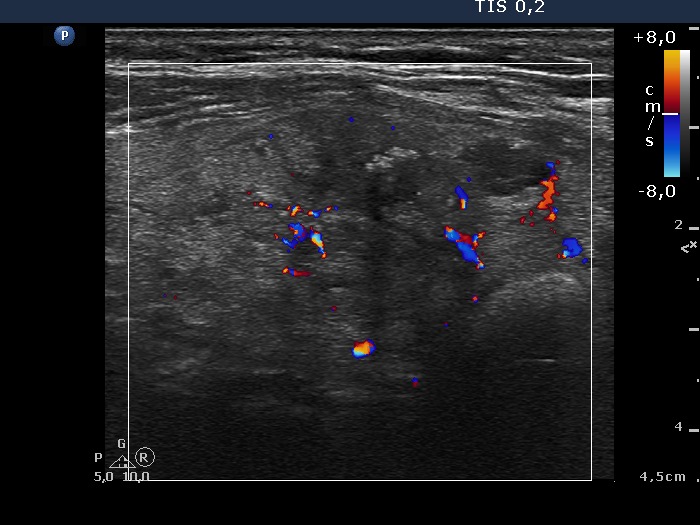

Follow-up investigation 8 month later (second row of images)

Clinical data: the patient had no complaints.

Palpation: the nodule in the right lobe was significantly smaller compared with first examination.

Functional state: euthyroidism (TSH 0.96 mIU/L).

Ultrasonography. The thyroid was echonormal. The nodule was composed of multiple echonormal discrete lesion and lacked cystic fluid. The volume was 1/8 of the pretreatment size.

Suggestion: yearly follow-up.